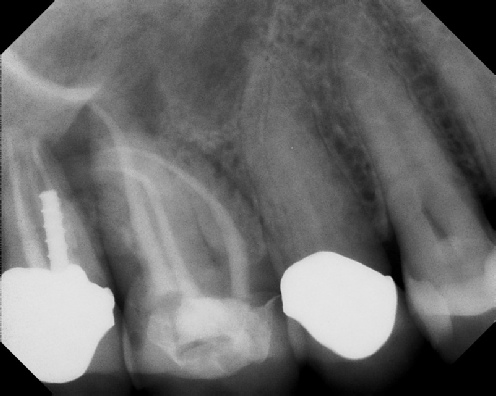

Root Canal Retreatment - Meriden 8 mos. recall Post-op Pre-op